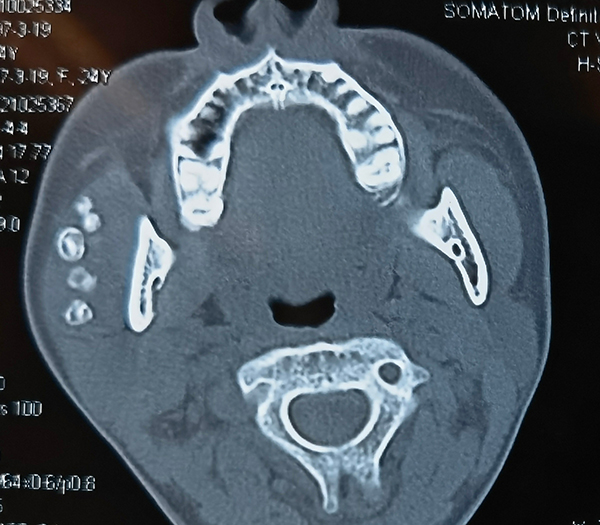

小珍的病史和相關影像學檢查提示右腮腺區靜脈畸形,頜面部CT提示靜脈畸形腔內有多個靜脈石。口腔頜面外科何滸杰醫師作為小珍的管床醫生,非常細心、耐心和小珍講解病情,減少她對手術的恐懼。